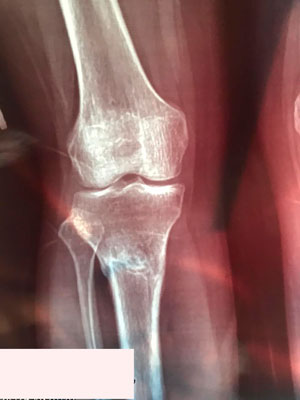

Исходник - 38 лет. Алматы.

Дата операции - 15.06.2019г.